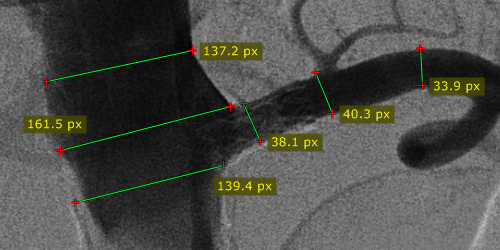

测量结果以毫米或像素显示(当图像文件中不包含校准数据时以像素显示)。

根据校准数据的来源不同,测量标注标签会以不同颜色显示:

已校准(图像中包含像素间距元素)。

距离使用估算的放射影像放大倍率计算。

距离在探测器平面上测量。

使用超声区域校准数据。

用户已执行手动校准。

无校准数据(测量结果为原始 DICOM 图像的像素数)。